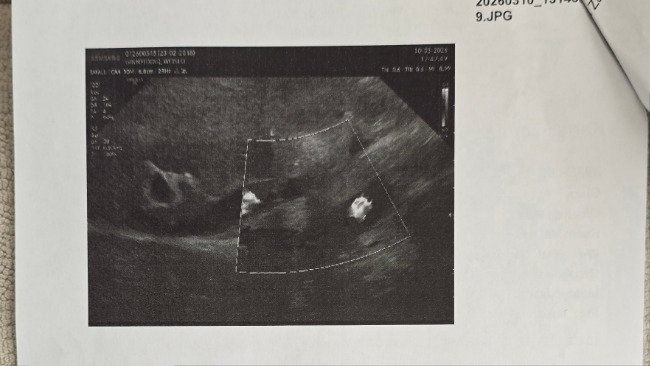

W ostatnim czasie, podczas kontrolnej wizyty Ginny u weterynarza, opiekunowie usłyszeli druzgoczącą wiadomość: guz prawego nadnercza. Potem ujawniono jeszcze nieładne nacieki na żyłę główną (CVC) i wątrobę. W dodatku dokładne zdiagnozowanie, czy guz jest operacyjny okazało się bardzo trudne.

Ginny przeszła już wiele kosztownych badań: